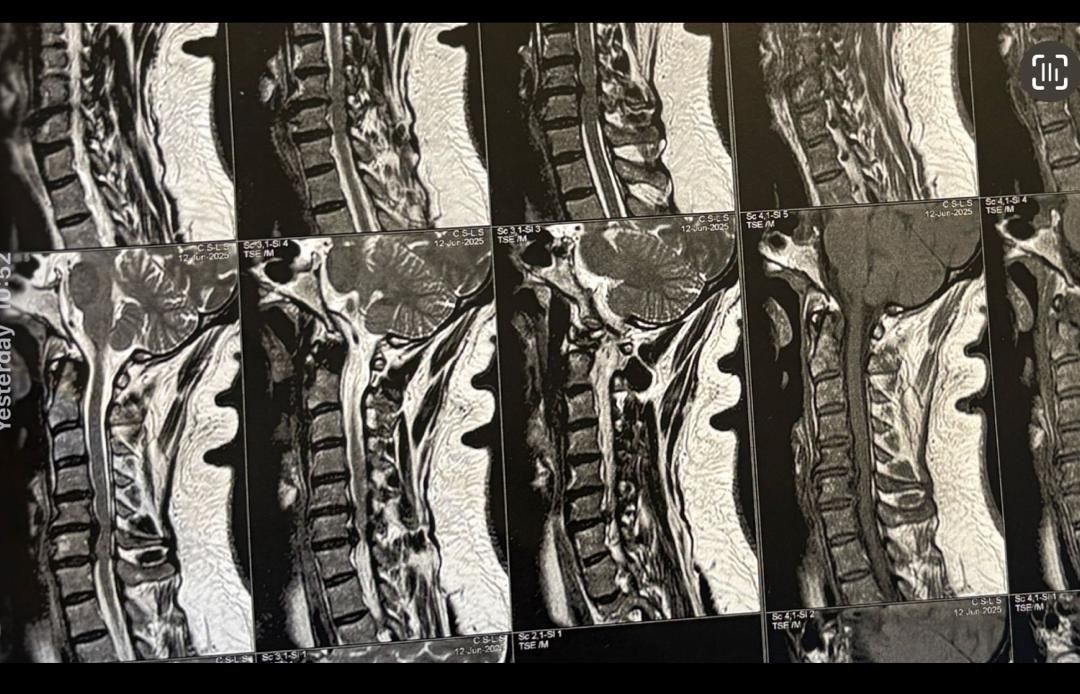

40 yrs old female patient presented to my clinic 2 hrs ago on May 18/2024 with severe neck and R upper extremity pain along C6 dematome. Had 12 sessions of PT with almost 20 percent improvement in her pain. Still has severe pain. I ordered EMG/ NCV( result showed moderate R c6 radiculopathy with no axonal loss)

Her mri is posted. i have started her treatment with acupuncture and very gentle cervical decompression. In 3 months her mri will be repeated